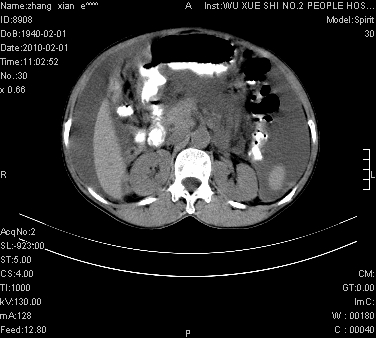

标题: CT24434:70岁 女 腹胀,腹水原因待查 [打印本页]

标题: CT24434:70岁 女 腹胀,腹水原因待查

大量腹水,脾脏囊性占位,子宫颈占位,右侧腹股沟淋巴结肿大,建议+c,先查妇科。

腹盆腔大量积液,子宫增大,子宫颈增大外形不规则,内见低密度影,膀胱后壁显示不清,右腹股沟肿大淋巴结,脾脏囊性占位,子宫颈占位,子宫颈癌?建议增强。

考虑:1、腹膜转移,大量腹水;

2、脾占位性病变;

3、左侧卵巢占位性病变,建议增强进一步检查。

考虑:1、腹膜转移,大量腹水;2、脾占位性病变;3、左侧卵巢占位性病变,建议增强进一步检查。支持